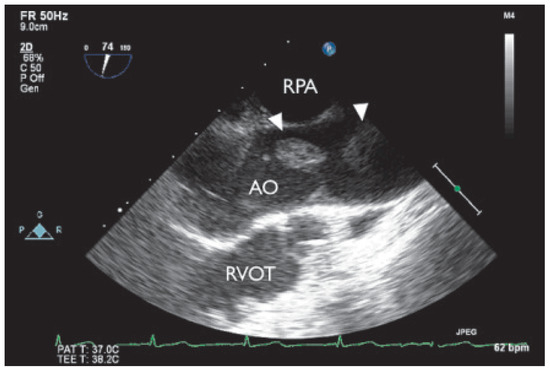

When Apical Is Parasternal, Or "Where Is the Heart?"

by Thilo Burkard and Beat A. Kaufmann

Cardiovasc. Med. 2015, 18(7-8), 226; https://doi.org/10.4414/cvm.2015.00345 - 12 Aug 2015

Viewed by 147

Abstract

A 57-year-old male presented to the medical outpatient department with typical angina pectoris Canadian Cardiovascular Society (CCS) class II and dyspnoea on exertion during the previous weeks [...] Full article

Show Figures

Figure 1